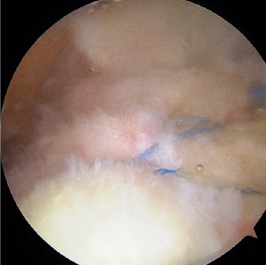

肩腱板断裂

関節鏡下腱板修復術